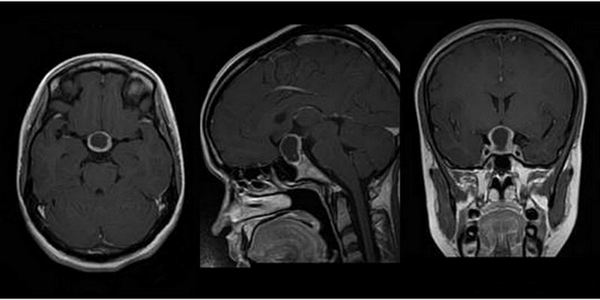

Выявление микроаденомы гипофиза с помощью МРТ: изображения в разных проекциях

Магнитно-резонансная томография обеспечивает сканирование области турецкого седла в трех взаимно перпендикулярных проекциях. Послойные монохромные снимки детализируют состояние анатомических структур зоны интереса, показывая малейшие изменения формы, размера, строения рассматриваемого объекта.

Микроаденома гипофиза (указана стрелкой) на снимке МРТ

На основании полученных изображений врач может реконструировать 3D-модель, позволяющую определить расположение сканируемых образований, взаимодействие здоровых и пораженных тканей.

Микроаденома гипофиза на снимках МРТ имеет ряд характерных признаков:

- неоднородная структура;

- округлая форма;

- очаг имеет гипоинтенсивный сигнал на Т1-взвешенных изображениях;

- выраженная граница, отделяющая образование от здоровых тканей;

- при наличии кровоизлияний и кист наблюдается усиление сигнала на Т2-взвешенных изображениях.

Томограммы позволяют уточнить размеры и расположение очага. При локализации опухоли в турецком седле говорят о эндоселлярной аденоме. Образования, выходящие за пределы костного кармана, называют эндоэкстраселлярными.

Для лучшей визуализации микроаденомы применяют динамическое контрастирование. Метод подразумевает использование короткого временного промежутка, когда велика разница сигналов между новообразованием и участками с нормальной структурой. На снимках МРТ с динамическим усилением аденома гипофиза в первой фазе исследования выглядит как гипоинтенсивный очаг на фоне умеренно контрастирующих здоровых тканей железы.